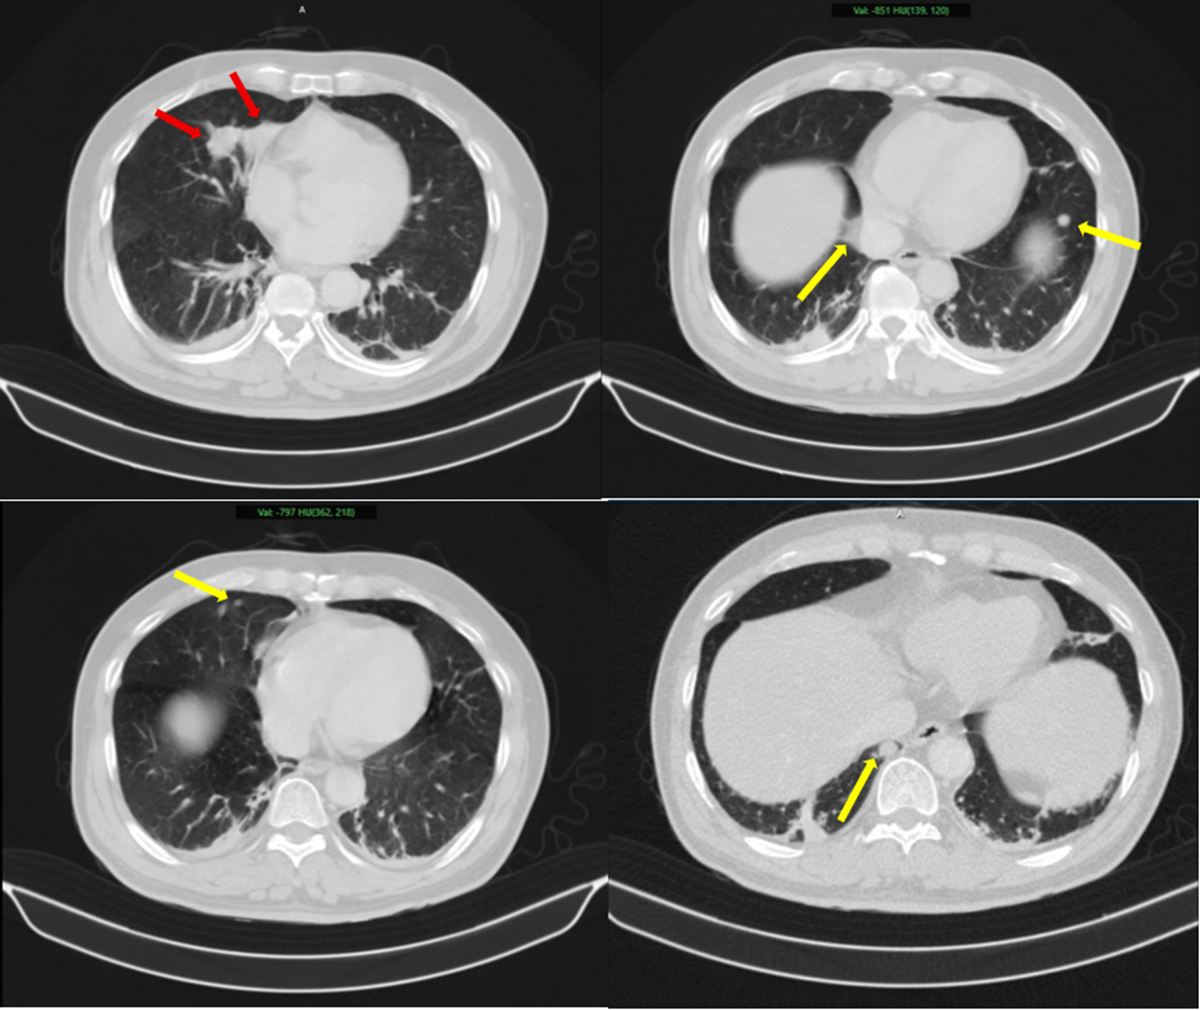

Hình ảnh 2 khối u bờ đa cung ở nhu mô thùy giữa phổi phải, dính vào màng phổi trung thất (mũi tên đỏ) kèm nhiều nốt đặc nhỏ rải rác nhu mô phổi hai bên (mũi tên vàng) gợi ý tổn thương thứ phát. Ảnh: BV Bạch Mai.

Tại viện kết quả sinh thiết và phân tích mô bệnh học kết hợp hóa mô miễn dịch giúp làm rõ: khối u phổi là ung thư biểu mô tuyến của phổi, trong khi khối u tuyến tiền liệt là ung thư biểu mô tuyến với điểm Gleason 9 - thuộc nhóm nguy cơ cao. Hai loại ung thư này có nguồn gốc hoàn toàn khác nhau, không phải di căn chéo.